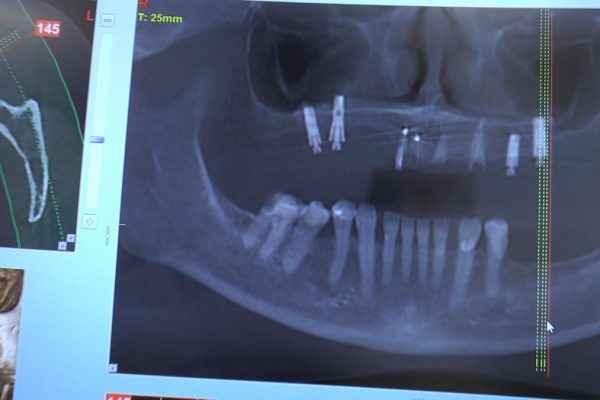

W ostatni weekend czerwca 2018 roku kursanci II Sezonu Preludium Implantologii odbyli piątą, finałową sesję, która w całości podporządkowana była praktyce. W ciągu dwóch dni zabiegowych Lekarze uczestniczący w szkoleniu przeprowadzili szereg zabiegów pod kierunkiem dr n.med. Violetty Szycik. Wszczepili 17 implantów oraz przeprowadzili ekstrakcje i zabiegi regeneracyjne kości. Zabiegi były wykonywane także w sedacji dożylnej z udziałem specjalisty anestezjologii i intensywnej terapii dr Jolanty Grzybowskiej. Preludium implantologii to nowy program edukacyjny dla adeptów implantologii stomatologicznej, którego celem jest wprowadzenie do implantologii poprzez pozyskanie wiedzy w szerokim zakresie i uwzględnieniem szczegółów mających decydujące znaczenie dla powodzenia leczenia implantologicznego. Ale tak jak wszystkie szkolenia w Instytucie Vivadental, w tym wiodące Practiculum Implantologii, zorientowane jest na praktyce i samodzielnym wykonywaniu zabiegów pod kierunkiem Mentora. To najlepsza edukacja w medycynie zabiegowej, a zarazem najlepszy start do implantologii.